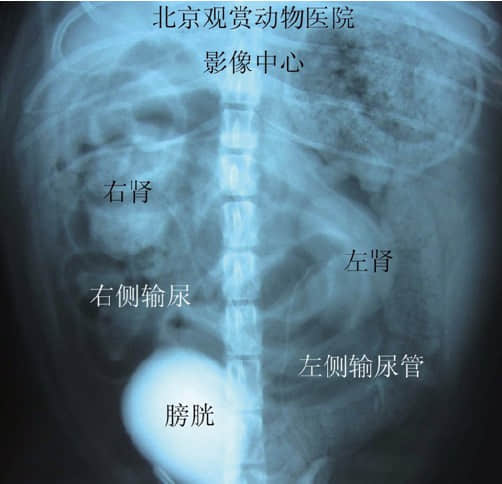

图3. 病犬输尿管犬造影后腹背位影像,可见右侧肾盂扩张。

图4. 正常犬输尿管造影后腹背位影像